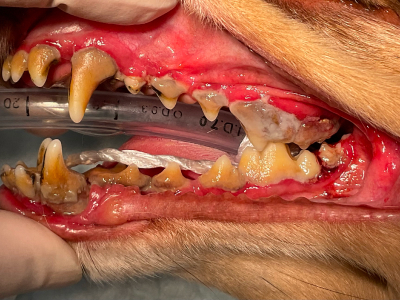

初診時

歯が触れる頬粘膜にびらんが起きています。

麻酔下で徹底的な口腔内清掃をするときれいに治りましたが、自宅ケアで少しでも歯垢の取り残しが出来るとまたすぐに再発し、かなり歯垢にデリケートなタイプのようです。 -